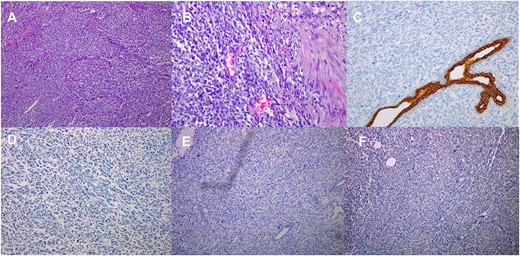

Paraffin blocks were brought for case revision as per hospital policy. Histopathology examination (Fig. 4) showed features keeping with high-grade sarcoma, with sections showing spindle cell tumor and prominent cytological atypia. Small foci of entrapped benign epithelial breast tissue were seen, wide areas of necrosis were present, and the mitotic index was about 30/10 per high-power field. Immunohistochemistry stains showed neoplastic cells positive for vimentin and focally positive for epithelial membrane antigen (EMA), negative for pan-cytokeratin (CK), CK7, estrogen receptors (ER), CD56, calretinin, c-KIT, and B-catenin. Ki67 positive in about 80% of tumor cells. The possibility of malignant phyllodes tumor could not be ruled out.

Histological images (10 × magnification) of the formalin-fixed paraffin-embedded sections (A) shows malignant spindle cell tumor with prominent cytological atypia. (B) shows malignant spindle cell tumor with prominent cytological atypia and pleomorphism. (C) Immunohistochmeically-stained slide of Ckpan showing negative reaction of tumor cells. (D) Immunohistochmeically-stained slide of ER showing negative reaction of tumor cells. (E) Immunohistochmeically-stained slide of desmin and myogenin showing negative reaction of tumor cells. (F) Immunohistochmeically-stained slide of CD56 showing negative reaction of tumor cells.